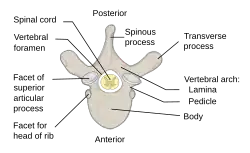

The spinal cord is housed in a bony hollow tube called the vertebral column.[3] The vertebral column is composed of many ring-like bones called vertebra (plural: vertebrae) and it spans from the skull to the sacrum. Each vertebra has a hole in the center called the vertebral foramen through which the spinal cord traverses.[3]

Laminae (singular: lamina) are the anatomical structures of primary importance in a laminotomy. Laminae are part of the vertebral arch which is the region of bone on the back side of each vertebra that forms a protective covering for the back side of the spinal cord.[3]

The vertebral arch is composed of several anatomical features in addition to laminae that must be taken into account when performing a laminotomy. In the center of the vertebral arch is a bony projection called the spinous process.[3] The spinous process is located on the posterior or back side of the vertebra and serves as the attachment point for ligaments and muscles which support and stabilize the vertebral column.[3] Each vertebra has two lateral bony projections called the transverse processes which are located on either side of the vertebral arch. Transverse processes come into contact with the ribs and serve as attachment points for muscles and ligaments that stabilize the vertebral column.[3] The lamina is the segment of bone that connects the spinous process to the transverse process. Each vertebra has two lamina, one on each side of the spinous process.[3]